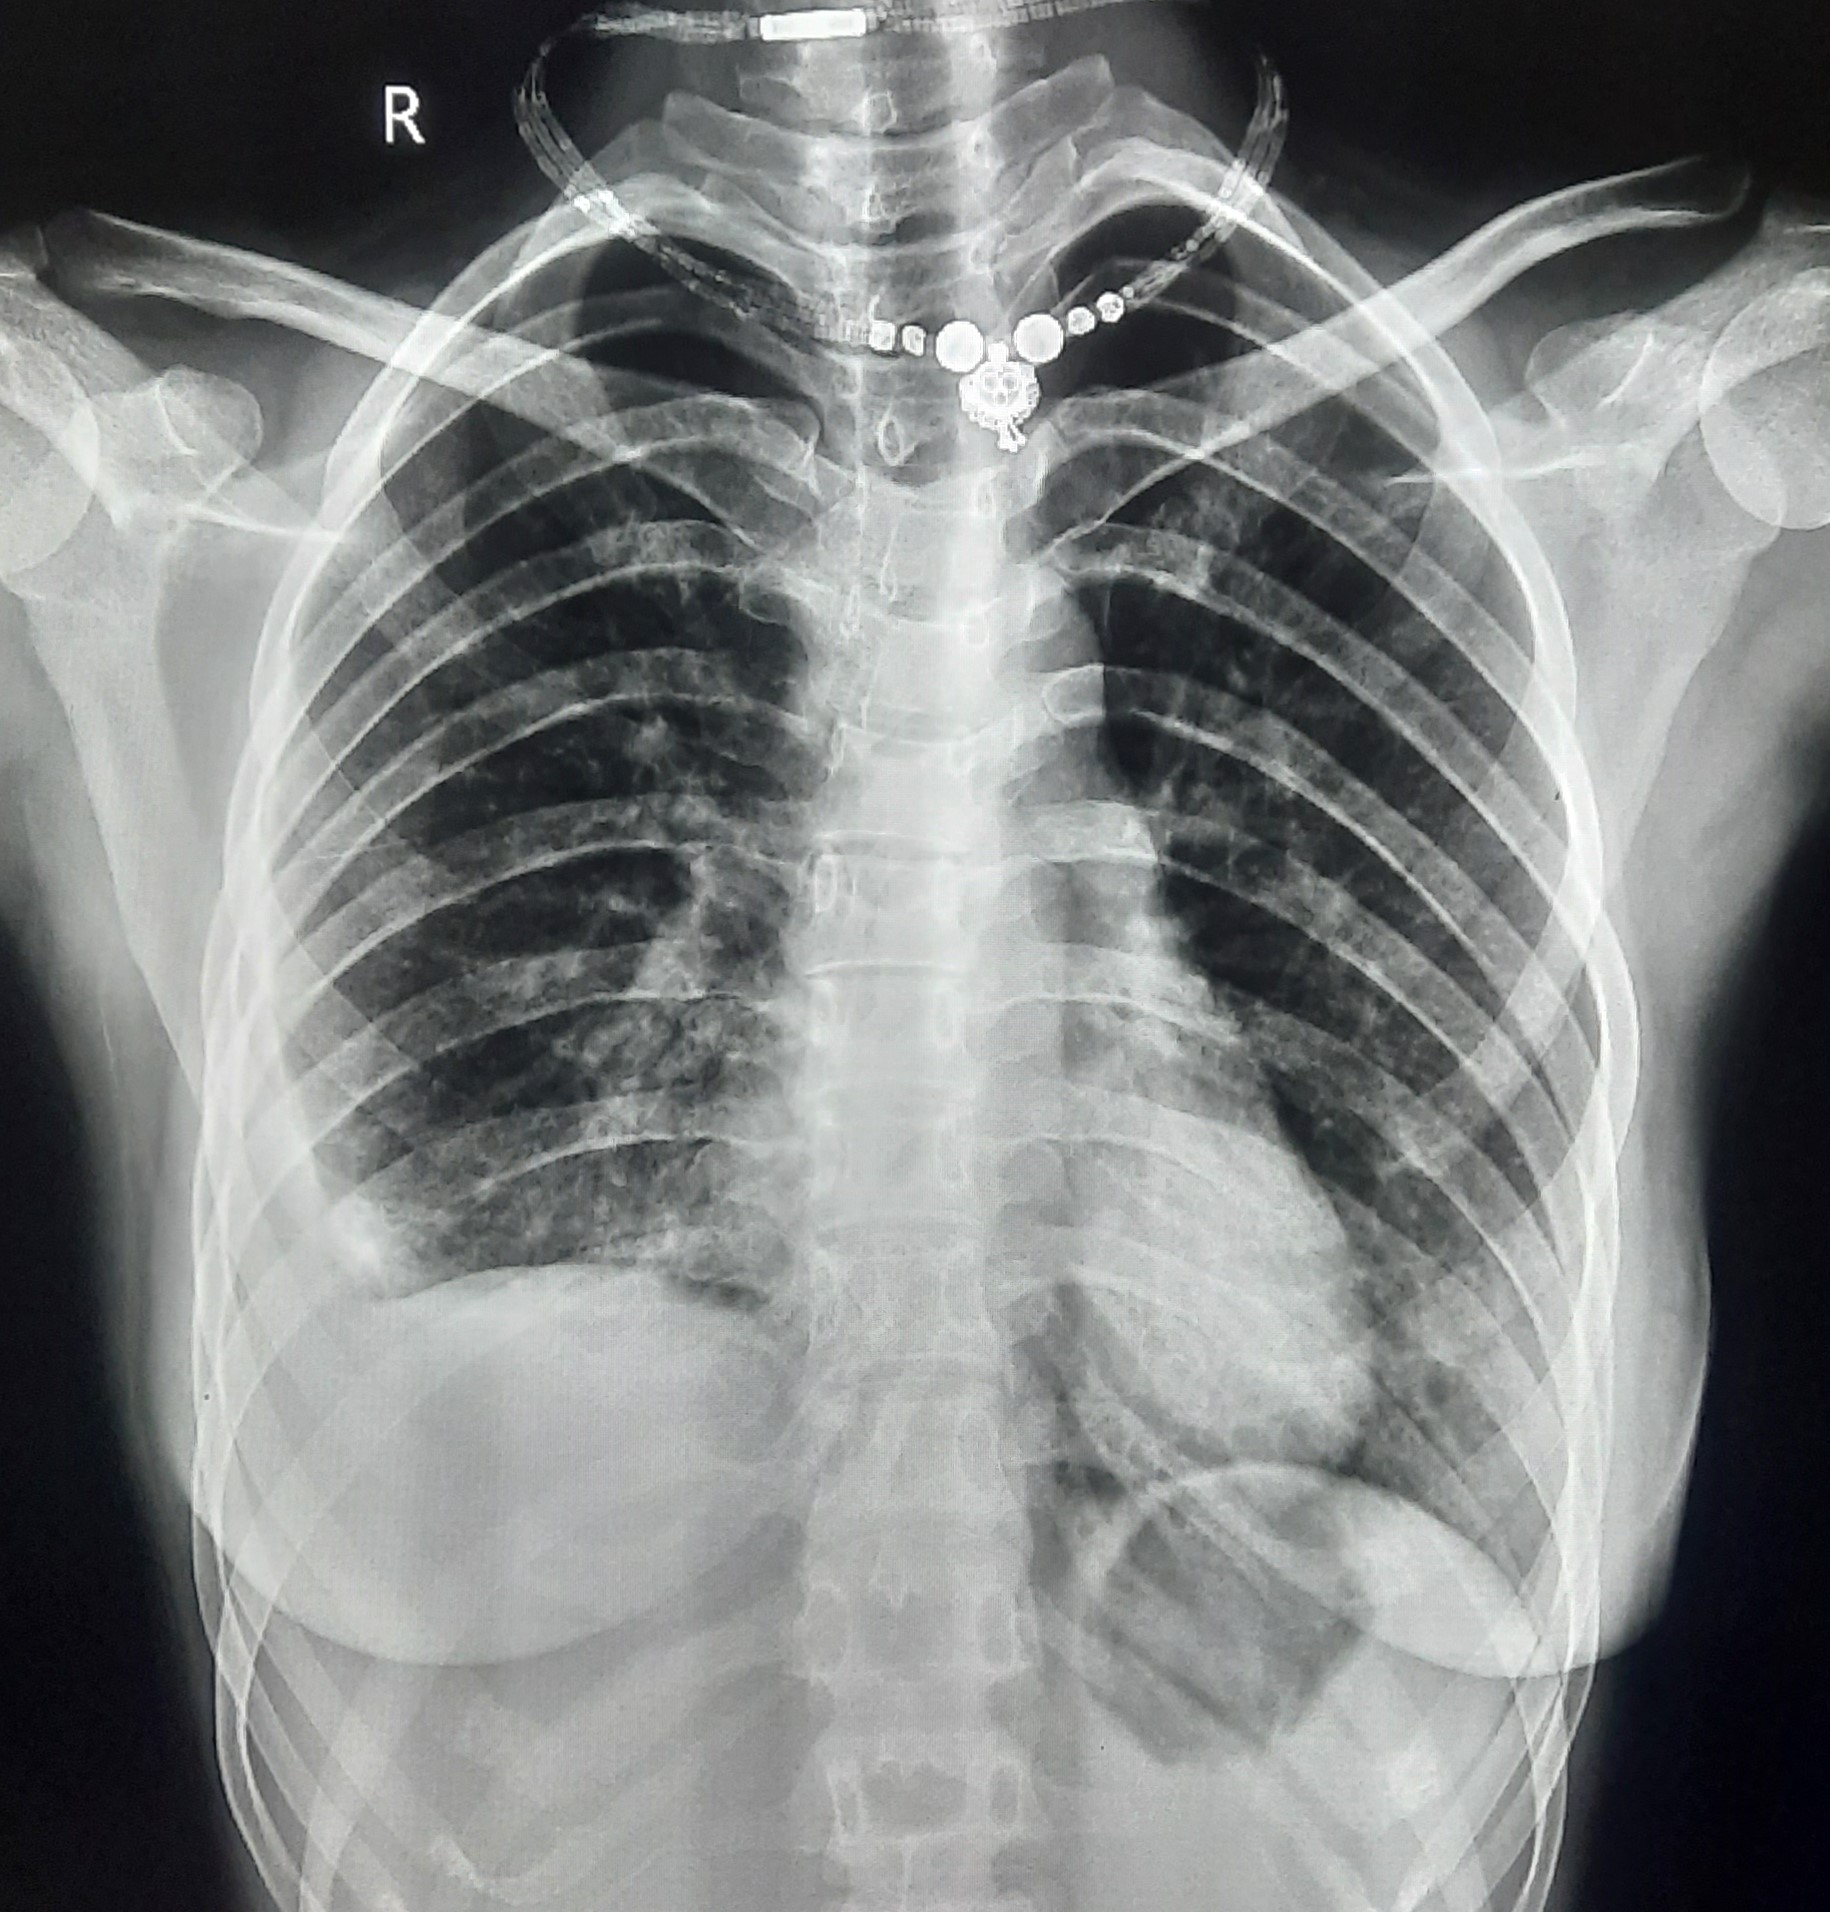

| 53 | IGGMC, Nagpur, Nagpur | P2 | 29-4419 | Rasul Ali | Consent taken on Paper | 36 Yrs. |

Provisional Diag : ?

Final Diag : COPD |

Non-TB Case (Confirmed) | Prominence of broncho vascular markings in bilateral Mid zone il Defined Non-Homogenous Lesion, Changes Of COPD | Abnormality visible on x-ray |